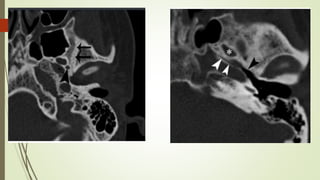

• #38 Izqu. AXIAL-- fxLongitudinal perdonan la capsula otica (laberinto oseo) Centro AXIAL fx trnasversa lascuales tperdonan el lab erinto oseo Dere: MIXTA – tmp perdona

• #50 IZQ: Sutura esfenoescamoosa,, lateral al foarmen espinoso(punta de flecha) DDER: sutura esfenopetrosa: foramen oval(astericos), trompa eustaqui (punat negra)

• #51 IZQ: Canal arqueado(petromastoideo) . Canal SC superior DER: Hiato del facial(blanca), ganglio geniculado (negra)